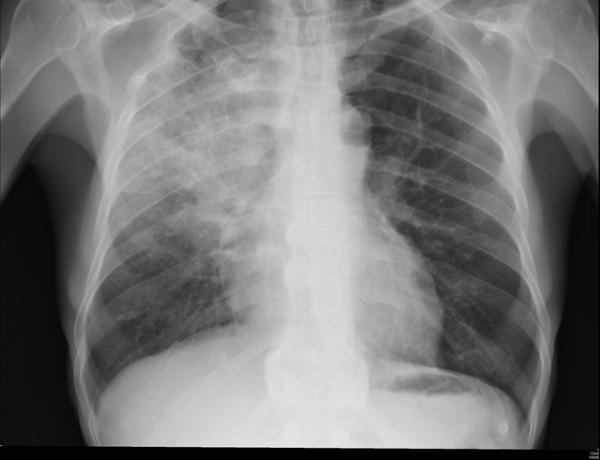

With that context in mind, the researchers studied patients treated in the hospital for pneumonia. The study involved the Michigan Hospital Medicine Safety Consortium, a network about 50% of Michigan’s nonfederal hospitals. [1] Patients all had a diagnosis of community or hospital-acquired pneumonia, evidence of pneumonia on examination and at least a 4-day hospital course of antibiotics. [2] Excessive days were defined as any course of treatment longer than national guidelines, and because of the vagaries in how this data is computed, you were compliant if the prescription was within a day of the recommendation. Outcomes came from medical records as well as 30-day follow up telephone conversations with patients. The study included 87% of eligible patients, roughly 6500 with a median age of 70, and about 75% had a community-acquired pneumonia. [3]

It is interesting to note which patients were excessively treated, it is, to my mind, a window into physician thinking. In general, excess therapy was directed at “high risk” patients. High risk was not quantified but impugned by a longer hospital stay, patients with positive diagnostic testing especially those with worrisome symptoms like producing phlegm, patients who had already been on antibiotics within the last 90 days who might have a "superinfection," academic affiliation and inadequate documentation of the length of treatment before discharge.